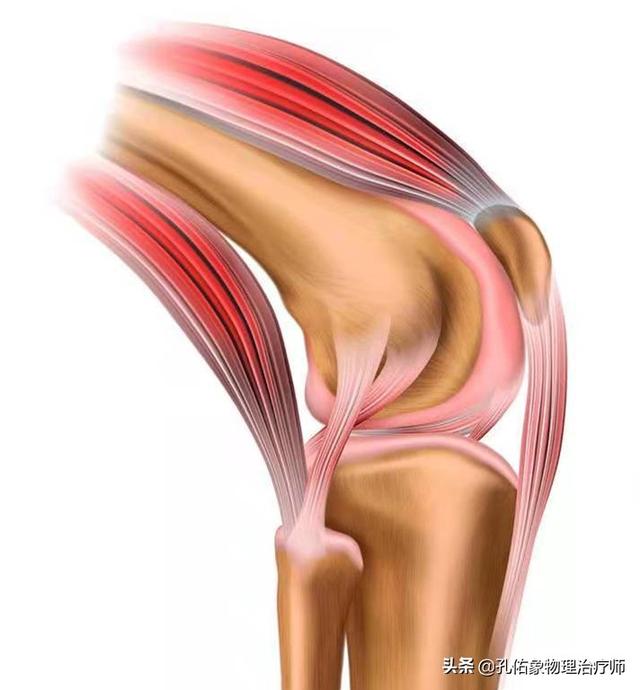

この病気は、骨や関節、関節軟骨の問題だけでなく、膝関節周囲の腱、靭帯、膝蓋骨なども負担や炎症によって刺激され、痛みや不快感を引き起こす。

膝関節は体重のかかり方に特徴があり、社会活動やスポーツをする際にその負担は大きくなる。 膝関節が柔軟であり、かつ大きな負荷に耐えるためには、周囲の筋肉の複雑な構造がカギとなる。膝の冷えや痛み、ポキポキは、膝関節の構造で十分説明できます。

膝関節の伸展構造

私たちは二本の脚を頼りに歩いているのだから、膝関節を伸ばして重心を移動させなければならない。膝は後方に曲げることができるが、膝関節の安定性を維持するために、前方や側方への可動性は原則的にない。この安定性を維持するための基本は、膝関節に不可欠な4つの要素にある:

(i)動力源としての大腿四頭筋、(ii)膝蓋骨、(iii)膝蓋腱、(iv)脛骨結節からの作用点。